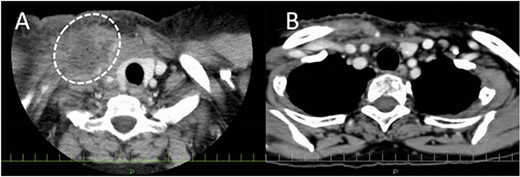

A 61-year-old female underwent right ND for recurrent oropharyngeal squamous cell carcinoma (rT0N2bM0). The postoperative course was uneventful, but the milky fluid was noted in the suction reservoir on POD1 (Fig. 2A). As the chyle leakage did not improve with administration of a fat-restricted diet, wound compression, and drainage, after aspirating as much retained lymph as possible using a syringe, 3KE of OK432 diluted in 6 mL of normal saline was injected from the right supraclavicular fossa on POD16. After OK432 injection, chylous leakage immediately stopped without any adverse events, such as fever and local pain (Fig. 2B).

Enhanced CT before and after OK432 injection. (A) Before OK432 injection. The lymph (dashed circle) is retained in the right supraclavicular fossa. (B) After injection. The lymphatic leakage disappeared after OK432 sclerotherapy.